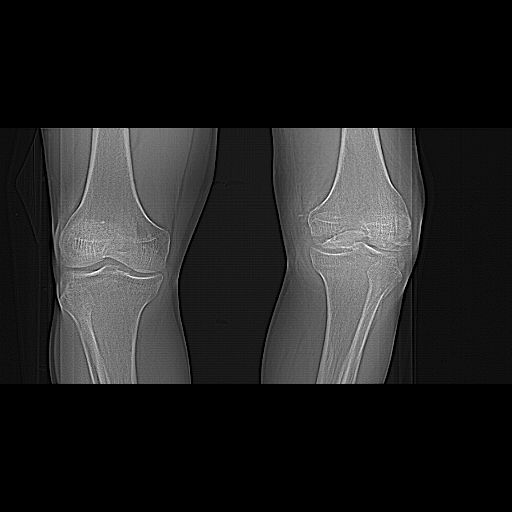

Качественные только исходные рентгенограммы (вышлю или завтра или в понедельник). Все последующие рентгенисследования были малоинформативны

(в т.ч. и последние снимки). КТ-исследование делалось 3 или 4 дня назад...

CT shows major bony fragments which are markedly rotated .With this amount of bony damage,you probably should attempt to get reasonably loooking knee with ORIF and thn if he needs a TKR due to pain a few years from now, then tleast you have something looking like a knee that you can replace rather than having to use revision knee for a primary TKR now. 4 weeks is not too long .what is the condition of soft tissues?

Before the CT and MRI era, we were treating the fractures with study of the Xrays alone. Such fractures with skeletal traction followed by non wtbearing mobilisation used to yield a fairly good range of movements. The CT gives a real ghastly picture of not so bad looking plain Xrays. I think this case needs traction to start with to correct the flexion deformity which probably will be achieved in 2 weeks time or less. We can then reassess the case with fresh Xrays. If possible one should try and fix the fragments to get some alignment. But the fixation should be stable enough to be able to mobilise the joint. Otherwise the traction can be continued for another 2 weeks to make the fracture sticky and then mobilise. We could get about 70 to 80* movements in spite of such communition. I am enclosing an Xray of a patient who is walking independantly and has 0 to 80* movemnts of the knee for the last one year

В общем, можно сказать, что срок 1 месяц после травмы слишком мал, чтобы ставить крест на суставе. Почему вообще мысли об артродезе, если есть возможность эндопротезирования? Ведь не год, а всего месяц после травмы, движения тут восстановить легко. То, что сейчас у больного сгибательная установка и болезненны попытки движений, не говорит о том, что уже 4-главая мышца рубцово перерождена и по всей длине прочно спаяна с бедренной костью, есть фиброз сустава и т.д.

У нас в клинике поступление больных в подобные сроки - не исключение, а правило. Через месяц и даже позже можно ожидать вполне приемлемый

результат хирургического лечения. Снимков детальных нет, так что только в общем - артротомия с отсечением бугристости, репозиция, если импрессия - костная пластика, фиксация пластинами и винтами, укладка в послеоперационном периоде в положение 90/90 на первые 2-3 дня, затем использование аппарата для Continuous Passive Motions или скользящей функциональной шины.